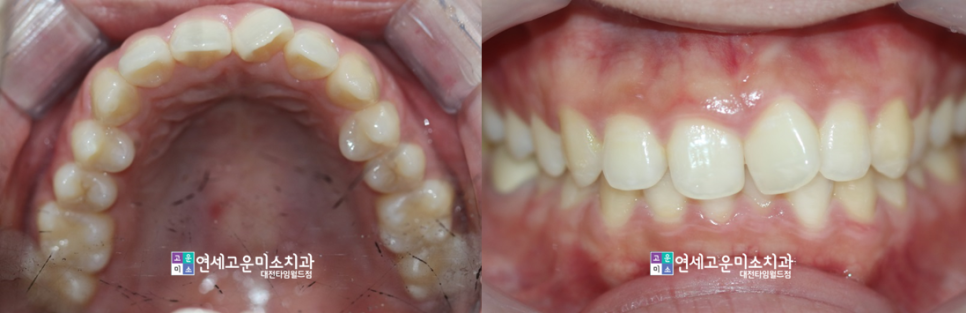

case1-1 ) 앞니만 불규칙해요

왼쪽 위에 첫 번째 앞니가 회전이

되어 있고 이것만 교정 받고 싶어서 오셨습니다

위에 환자분 케이스도 두 가지 요건을 모두 충족하였기에

부분교정으로 훌륭히 마무리가 되었습니다.